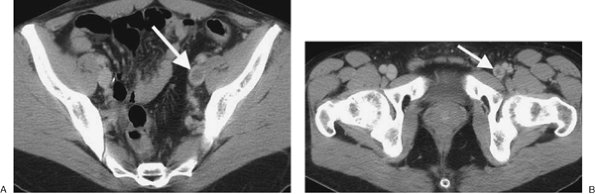

FIGURE 17-18. Deep venous thrombosis and acute PE. A: CTPA of a 66-year-old woman with an endometrial mass and left leg swelling shows bilateral PE. B: CTV performed immediately after the CTPA shows left DVT (arrow). C: CTV at a more inferior level shows expansion of the involved left lower-extremity vein and soft tissue stranding of the adjacent fat (arrow).

PE and DVT are different manifestations of the same clinical disease. One advantage of CTPA is the ability to add CTV, from the iliac crest to the tibial plateau, to detect DVT in the legs

and pelvis (Figs. 17-20 and 17-21). Both CTPA and CTV can be accomplished with the same bolus of contrast agent. Unlike lower-extremity ultrasound, CTV can image the external and internal iliac veins. Venous thrombosis can also occur in the upper extremities and in the thorax and can be detected on CTPA (Fig. 17-22).

FIGURE 17-21. Deep venous thrombosis. A: CTV of a 42-year-old man with protein C deficiency and recurrent DVT shows a filling defect within a left pelvic vein (arrow). B: CTV at a more inferior level shows thrombus within the left femoral vein (arrow).